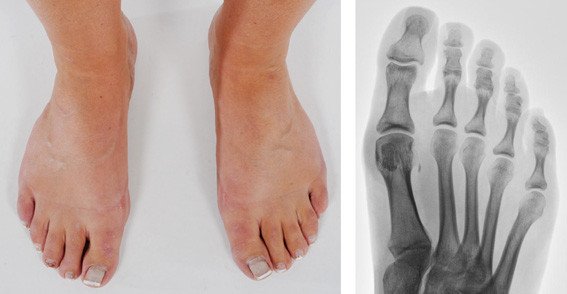

Ermüdungsbruch des Sesambeines am Grosszehengrundgelenk

Stressfrakturen ereignen sich bei immer wiederkehrenden Belastungen, wie sie das Lauftraining mit sich bringt und können sich auch an anderen Knochen des Fussskelettes entwickeln. Die Untersuchung des betroffenen Fusses zeigte einen deutlichen Druckschmerz unterhalb des Grosszehengrundgelenkes an der Fusssohle genau an der Stelle, an der sich das seitliche Sesambein befindet. Die restliche Fussuntersuchung war unauffällig.